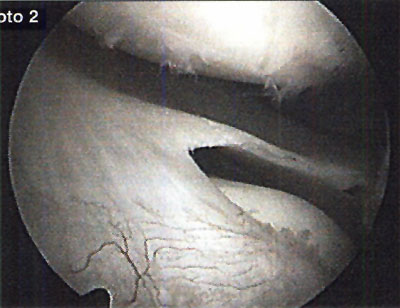

En cuanto a la localización de la lesión, 1 (2,4%) paciente presentó una localización anterior, 12 (29,3%) anterolateral, 23 (56,1%) posteromedial y 5 (12,2%) central. No se pudo explicar claramente esta distribución. (fotos 1 y 2) En cuanto a los casos presentados, los estudios radiográficos pusieron en evidencia la lesión en solo 36,6% de los pacientes, en 26 (63,4%) las radiografías fueron negativas (GI) mientras que de los casos positivos, 6 (14,6%) presentaron una lesión GIl, 6 (14,6 %) presentaron una lesión GIl y 3 pacientes (7,3%) una lesión G IV. (fotos 3 y 4)

Foto 1: lesión anterolateral

Foto 2: lesión posteromedial.